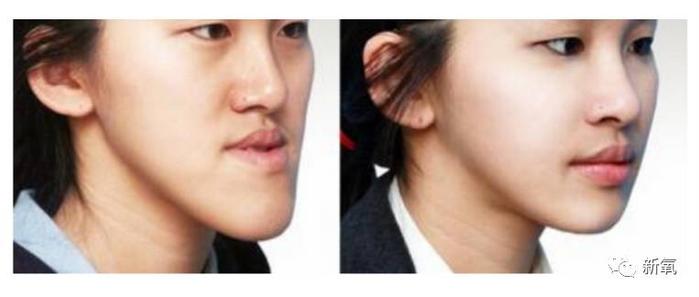

仔细看,这会儿的她是不是有点小龅牙?

来个同角度对比更明显。而且这期节目是09年播出,欧阳娜娜已经9岁,说明已经换完了牙。

再稍大几岁,她也开始像姐姐一样牙齿变得微龅起来,到了9岁就是文章开篇微微包不住的状态了。

后来开始整牙后,龅牙趋势被压了下来,到现在就变成了我们看到的、这个美美的牙弓弧度。

看下面这个真人案例,仅在整牙的矫正下,不仅下牙列回到正常的位置,连原本被限制发育、显得凹陷的中面部也变得正常,明显侧脸变得饱满了。

和地包天一样,因为涉及到骨骼问题,所以最佳矫正时间也比较早,基本上在换完牙的8-10岁就可以找牙科医生进行干预了。

和地包天是一样的原理,在骨骼成型前,将其用外力引导到正确位置。利用牙槽骨的改建能力,让颌骨发育问题得到改善。

李咏的女儿就是正面例子,小时候亮相被大家说丑颜值低。

后来矫正了牙齿,下巴也慢慢长了出来。